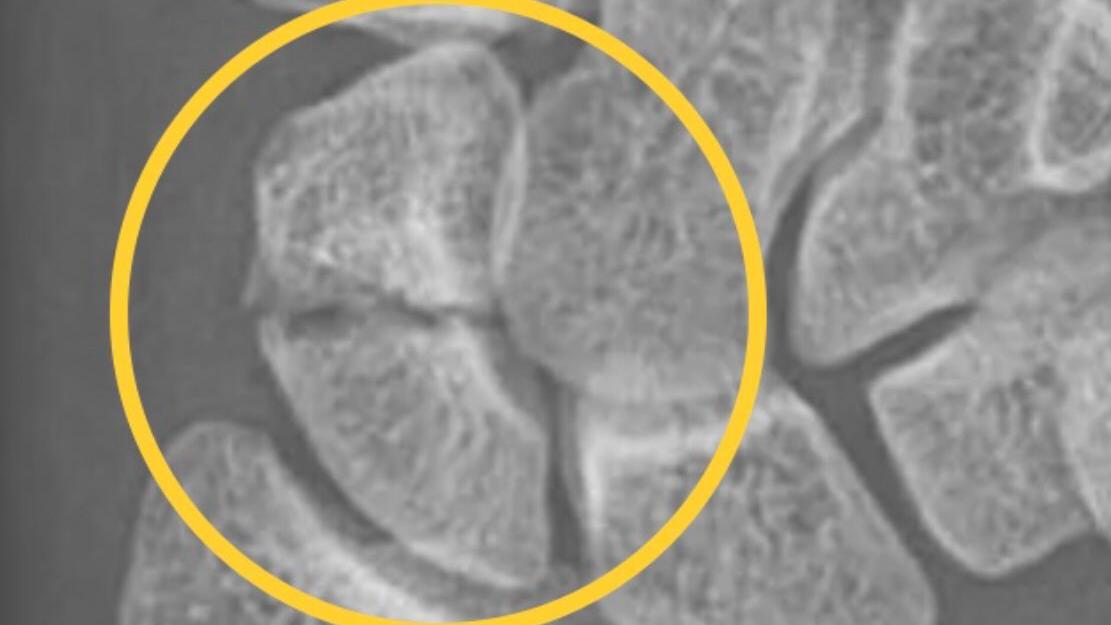

• 舟骨骨折

舟骨骨折「沉船」記

健康

3年前